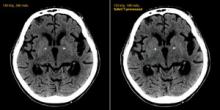

Computed tomography (CT) offers a very important, noninvasive diagnostic tool, but the price of high image quality sometimes comes with a cost of high radiation dose. This is especially true of CT angiography (CTA), which may require imaging several cardiac cycles.